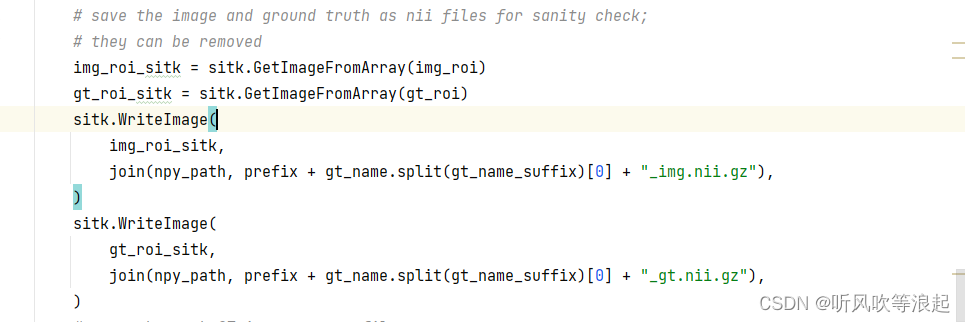

5.3.3 保存为npy格式

这里可以删除,不影响